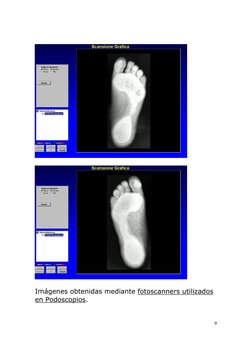

Imgenes obtenidas mediante fotoscanners utilizados en Podoscopios.

Imágenes obtenidas mediante fotoscanners utilizados

en Podoscopios.